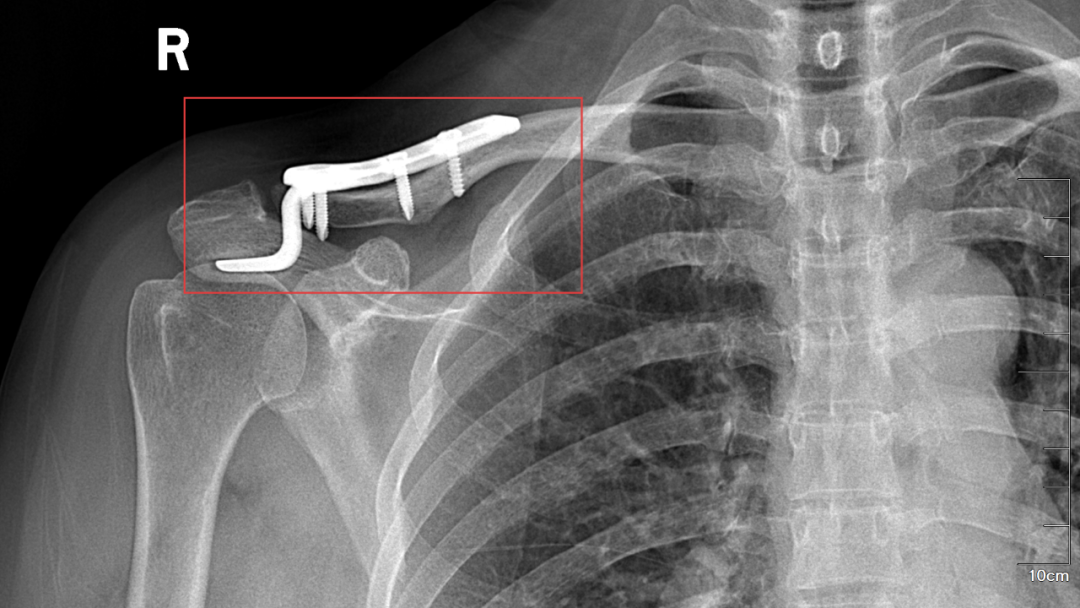

5月14日,玉溪市中山医院骨科为肩锁关节脱位术后患者武女士完成了内固定装置取出手术。一年前武女士因车祸导致右肩锁关节脱位 (III度),在玉溪市中山医院接受了“右肩锁关节脱位切开复位内固定术”,术后武女士积极配合医护团队治疗并顺利出院。此次术后一年复查,显示她的骨性愈合良好。骨科团队为武女士实施了精细化手术,顺利取出内固定装置,并通过精准操作确保患部功能完整恢复。术后,武女士恢复状况良好,于5月22日出院。为感谢周树文主任、杨鹏医师等医护团队,武女士赠送锦旗“妙手扶桑梓,高医攀新峰”,表达深切感激。

手术后